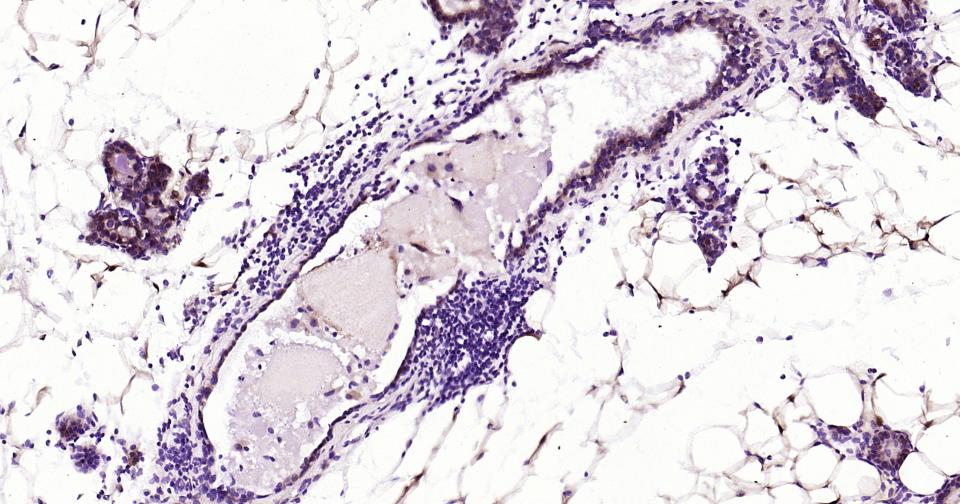

Paraformaldehyde-fixed, paraffin embedded Mouse Breast; Antigen retrieval by boiling in sodium citrate buffer (pH6.0) for 15 min; Antibody incubation with S100A1 Monoclonal Antibody, Unconjugated(bsm-63045R) at 1:200 overnight at 4°C, followed by conjugation to the bs-0295G-HRP and DAB (C-0010) staining.

Paraformaldehyde-fixed, paraffin embedded Human Chronic tonsillitis; Antigen retrieval by boiling in sodium citrate buffer (pH6.0) for 15 min; Antibody incubation with S100A1 Monoclonal Antibody, Unconjugated(bsm-63045R) at 1:200 overnight at 4°C, followed by conjugation to the bs-0295G-HRP and DAB (C-0010) staining.

Paraformaldehyde-fixed, paraffin embedded Human Ovarian Cancer; Antigen retrieval by boiling in sodium citrate buffer (pH6.0) for 15 min; Antibody incubation with S100A1 Monoclonal Antibody, Unconjugated(bsm-63045R) at 1:200 overnight at 4°C, followed by conjugation to the bs-0295G-HRP and DAB (C-0010) staining.

Paraformaldehyde-fixed, paraffin embedded Human Thyroid Gland Tumor; Antigen retrieval by boiling in sodium citrate buffer (pH6.0) for 15 min; Antibody incubation with S100A1 Monoclonal Antibody, Unconjugated(bsm-63045R) at 1:200 overnight at 4°C, followed by conjugation to the bs-0295G-HRP and DAB (C-0010) staining.

Paraformaldehyde-fixed, paraffin embedded Human Heart; Antigen retrieval by boiling in sodium citrate buffer (pH6.0) for 15 min; Antibody incubation with S100A1 Monoclonal Antibody, Unconjugated(bsm-63045R) at 1:200 overnight at 4°C, followed by conjugation to the bs-0295G-HRP and DAB (C-0010) staining.

Paraformaldehyde-fixed, paraffin embedded Rat Heart; Antigen retrieval by boiling in sodium citrate buffer (pH6.0) for 15 min; Antibody incubation with S100A1 Monoclonal Antibody, Unconjugated(bsm-63045R) at 1:200 overnight at 4°C, followed by conjugation to the bs-0295G-HRP and DAB (C-0010) staining.

Paraformaldehyde-fixed, paraffin embedded Mouse Heart; Antigen retrieval by boiling in sodium citrate buffer (pH6.0) for 15 min; Antibody incubation with S100A1 Monoclonal Antibody, Unconjugated(bsm-63045R) at 1:200 overnight at 4°C, followed by conjugation to the bs-0295G-HRP and DAB (C-0010) staining.

Paraformaldehyde-fixed, paraffin embedded Mouse Cerebrum; Antigen retrieval by boiling in sodium citrate buffer (pH6.0) for 15 min; Antibody incubation with S100A1 Monoclonal Antibody, Unconjugated(bsm-63045R) at 1:200 overnight at 4°C, followed by conjugation to the bs-0295G-HRP and DAB (C-0010) staining.

Paraformaldehyde-fixed, paraffin embedded Rat Cerebrum; Antigen retrieval by boiling in sodium citrate buffer (pH6.0) for 15 min; Antibody incubation with S100A1 Monoclonal Antibody, Unconjugated(bsm-63045R) at 1:200 overnight at 4°C, followed by conjugation to the bs-0295G-HRP and DAB (C-0010) staining.